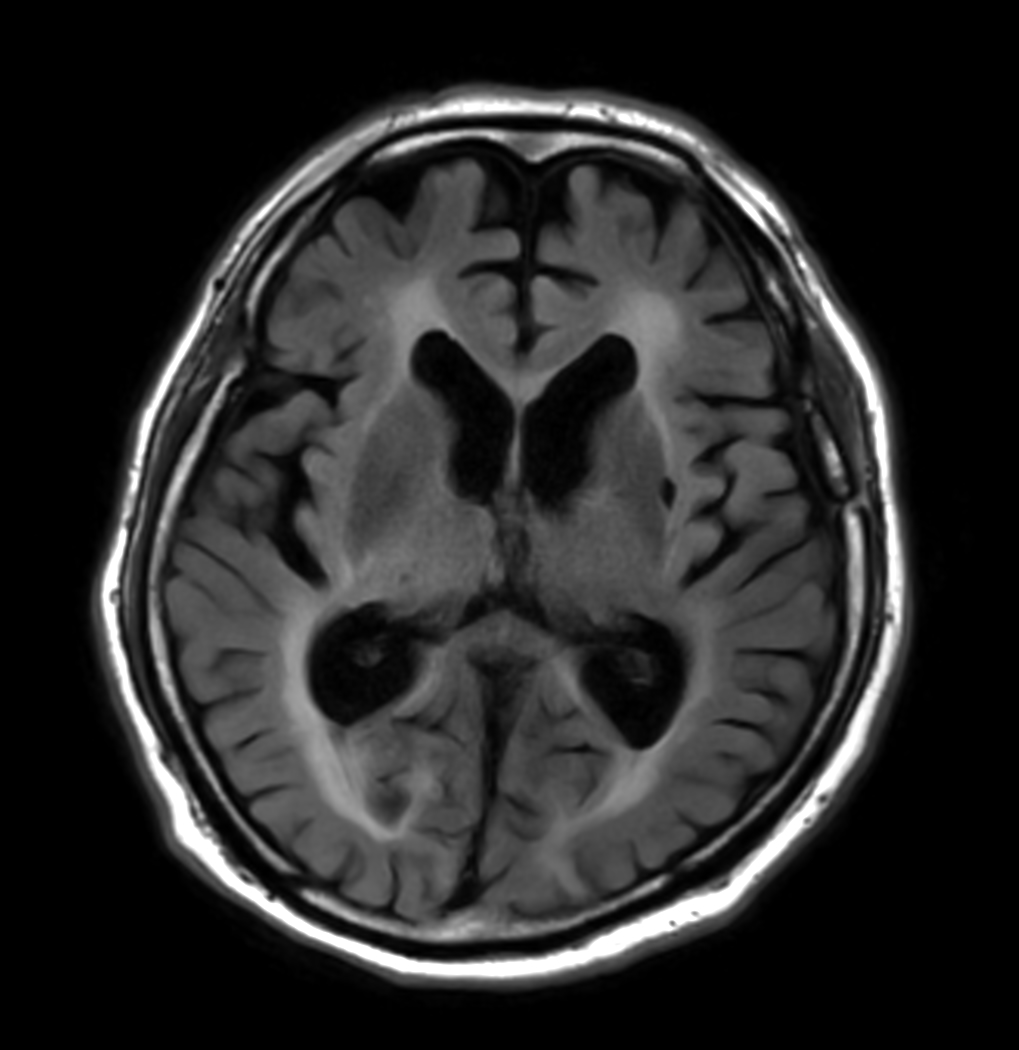

T2w FLAIR - MultiVane XD